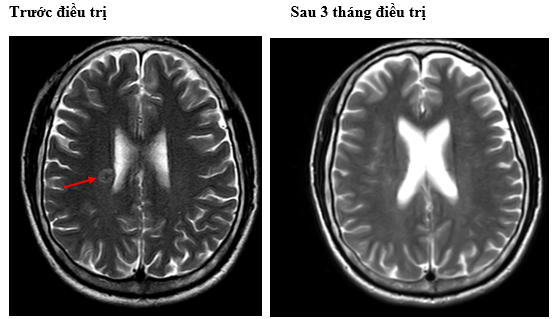

-         MRI sọ não:

Hình 4. Trên phim chụp MRI sọ não: Rải rác trong nhu mô trên và dưới lều có các nốt ngấm thuốc, lớn nhất vị trí cạnh não thất bên bên phải đường kính ~11mm – Theo dõi tổn thương thứ phát

Cộng hưởng từ sọ não:

Sau 6 tháng điều trị: Nhu mô não vùng trên và dưới lều tiểu não: hình dạng và cấu trúc bình thường, tín hiệu đồng nhất, ranh giới chất trắng và chất xám rõ. Không thấy tổn thương khu trú hoặc lan tỏa.